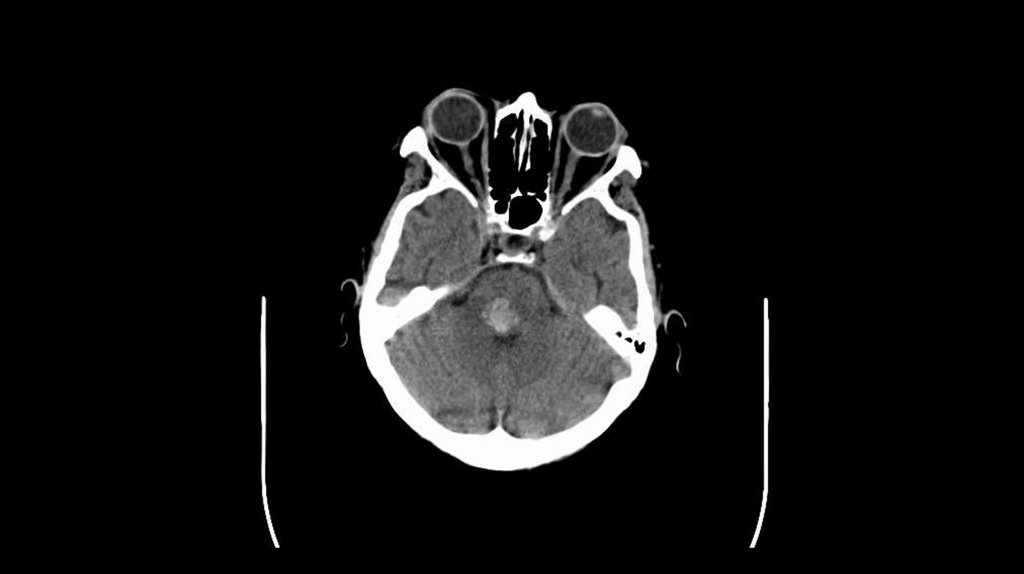

67 year-old woman

Presented with left sided

weakness

Slurred speech

Left facial droop

Double vision

BP: 210/110 mm Hg